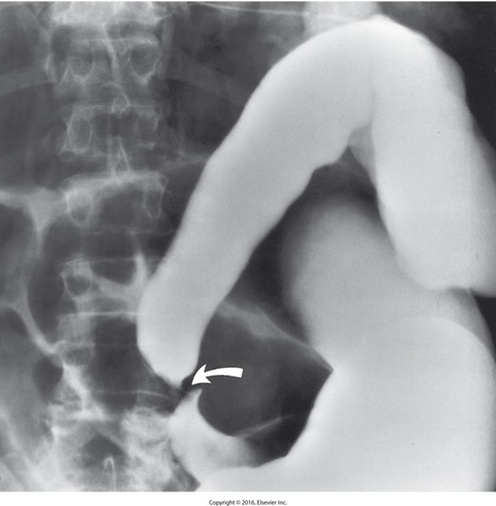

Colorectal Cancer

_____ is the third leading cause of cancer death in the United States.

Peak age incidence is 50 to 70 years old.

It is twice as common in men.

About half of colon carcinomas occur in the rectum and sigmoid.

Obstruction is a common finding

Predisposing factors:

Long-term ulcerative colitis (UD)

Familial polyposis (glandular polyps in the colon and rectum).

Radiological Appearance:

Apple core sign